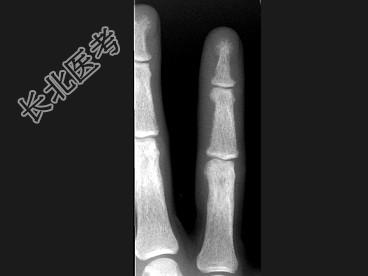

- 单项选择题女,41岁, 慢性肾功能不全,结合图像, 最可能的诊断是 ( )

B、甲状旁腺功能亢进